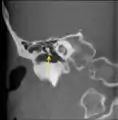

CT image of malleus